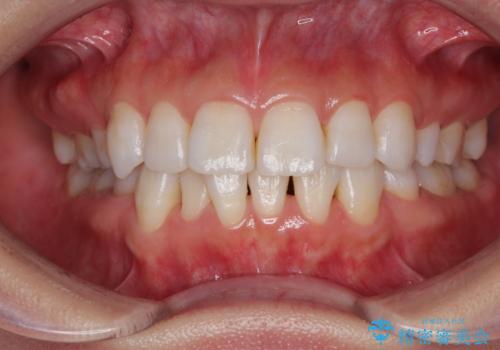

切端咬合をインビザライン矯正で解消

- 前歯のデコボコを気にして来院された患者様です。

上下前歯の先端同士が接触する切端咬合であったため、上顎は歯列を拡大し、下顎はIPR(歯と歯の間を削る)により叢生を解消しながら歯列を小さくすることとしました。

矯正装置にはインビザラインを用いることとしました。

治療途中に前歯に歯髄充血を思わせる痛みが認められたため、無理のない歯の移動と頻繁な経過観察を行いました。

切端咬合はスムーズに解消され、前歯の負担を軽減させることができました。